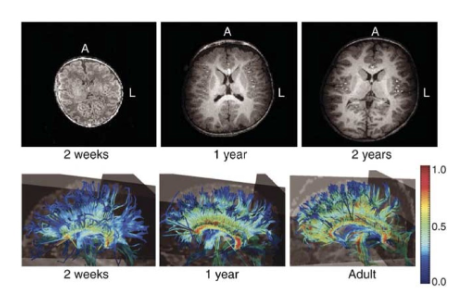

This is when myelin sheaths develop on the neurons, create from ogliodendrocytes

First occurs in the spinal cord and then the hindbrain midbrain forebrain.

This process continues under roughly the age of 18-21.